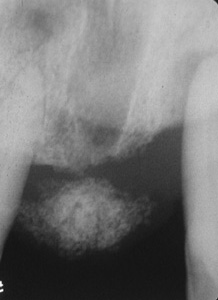

Radiografía de la lesión en la imagen anterior revela la formación de hueso, que no es un hallazgo raro en este tipo de lesión.

Esta microfotografía de baja resolución muestra  varios componentes del tejido. Hay áreas de tejido conjuntivo celular y zonas de inflamación crónica. Además, usted puede ver las numerosas trabéculas óseas que a  menudo están presentes.